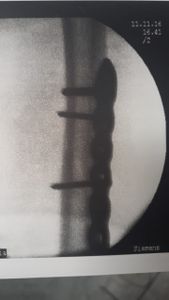

Foi uma fratura exposta onde eu usei a "gaiola" por quase 1 mês e depois fiz a cirurgia para a colocação da placa na extensão do fêmur e com 7 pinos no joelho.

- 1° retirada da placa do fêmur